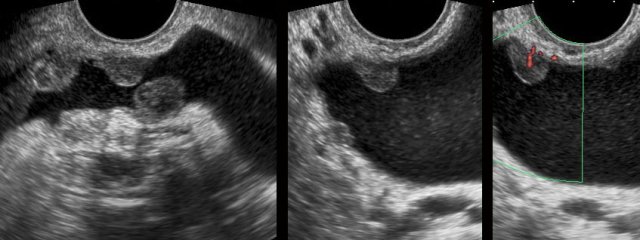

Secondary thickening of the distal ureteric wall after stone passage. Secondary thickening of the distal ureteric wall after stone passage.

A 58 year old woman had a left sided colicky attack, followed by a burning sensation during micturition as well as macroscopic haematuria. She lost some blood clots in the urine, but did not notice any stones. CT showed no stones. The sediment showed atypical urothelial cells.

TVUS showed  irregular wall thickening of the distal right ureter (arrowheads). The combination of these findings, raised the possibility of urothelial malignancy.

Seven days later, she was symptom free without any treatment, the urine sediment was normal again and follow up TVUS showed complete normalization of the distal ureter (arrowheads).

The final diagnosis was unnoticed stone passage with confusing secondary effects of  transient ureteric wall thickening and of abnormal urothelial cells in the sediment.